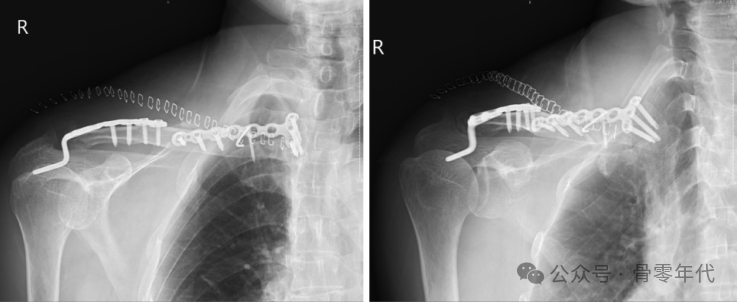

1例锁骨远端骨折伴锁骨近端脱位患者的影像表现。钢板内固定治疗双极锁骨损伤1例。利用杠杆复位锁骨两端,然后分别放置新的胸锁钢板和肩锁钢板。术后对患者进行影像检查。X线和CT图像